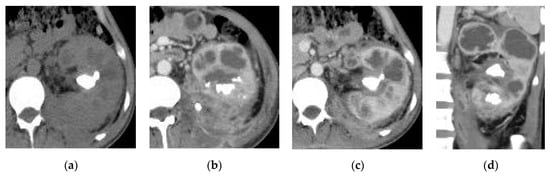

2.5. Xanthogranulomatous Pyelonephritis (XGP)

| Xanthogranulomatous Pyelonephritis | Non-functioning enlarged kidney, obstructing stone within a non-dilated renal pelvis, expansion of the calyces, and inflammatory changes in the perinephric fat. |